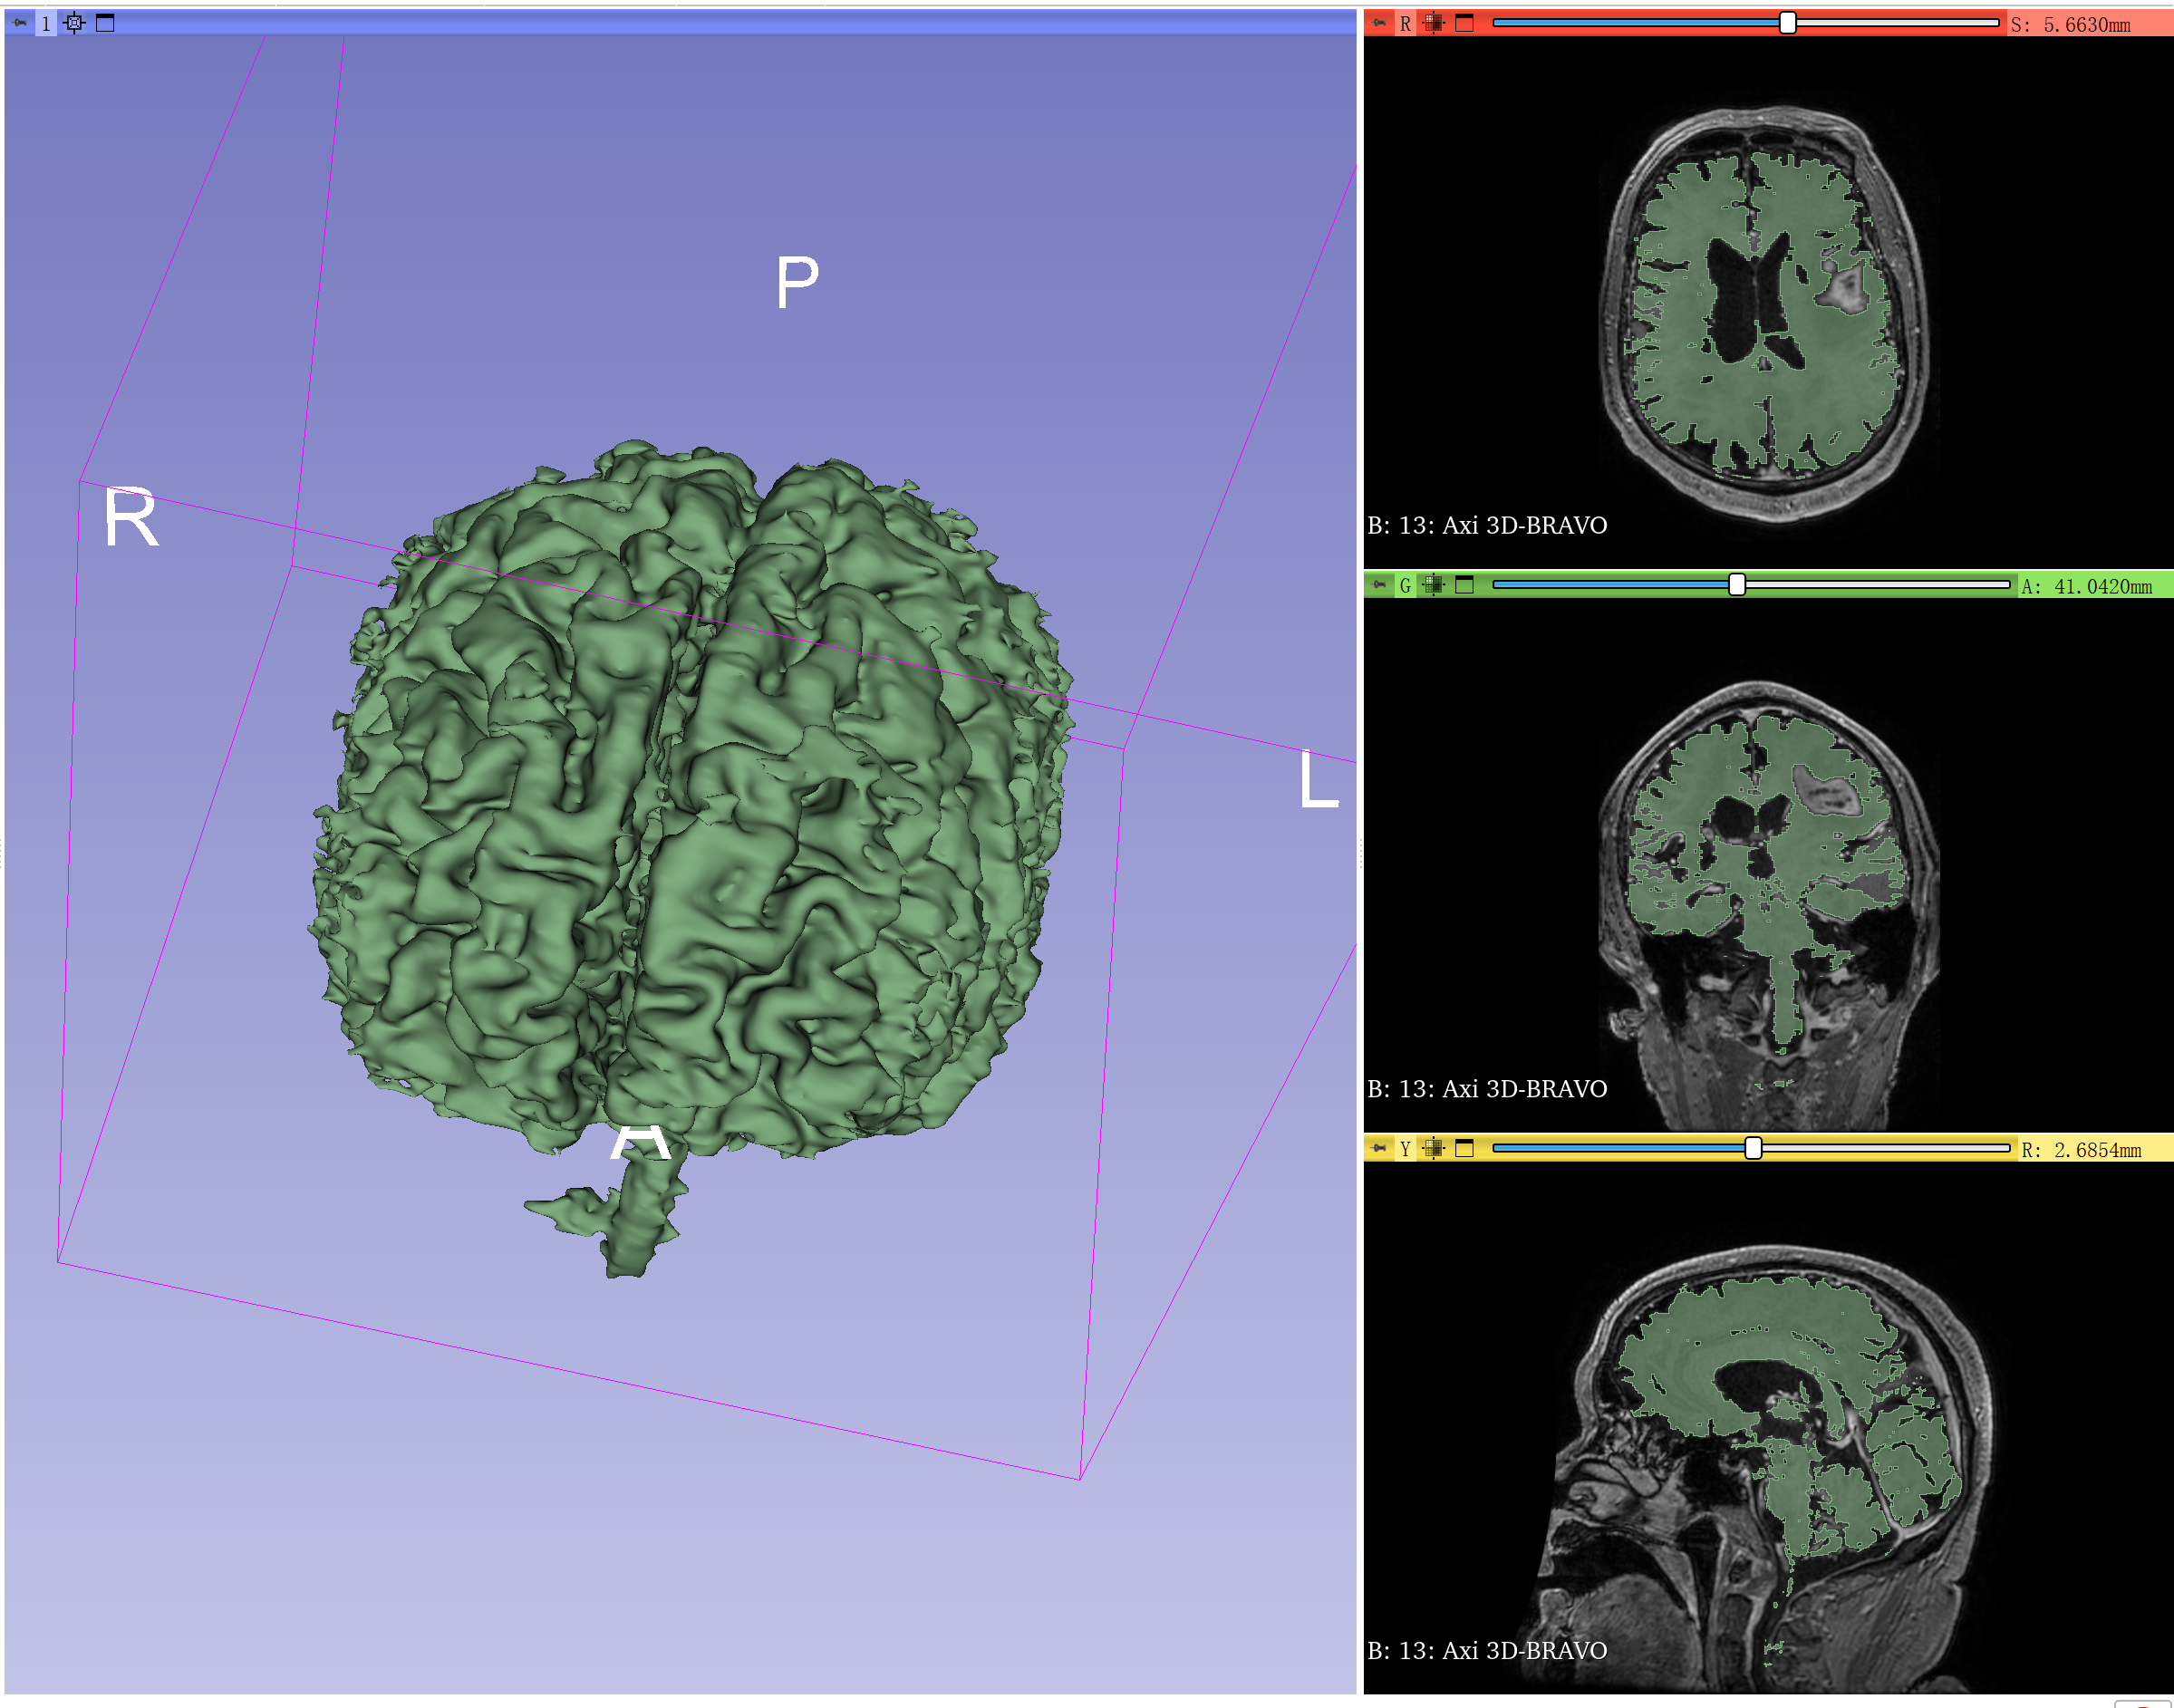

Initialize后点apply就可以得到下图的结果。

可以再用其他工具再修饰一下。